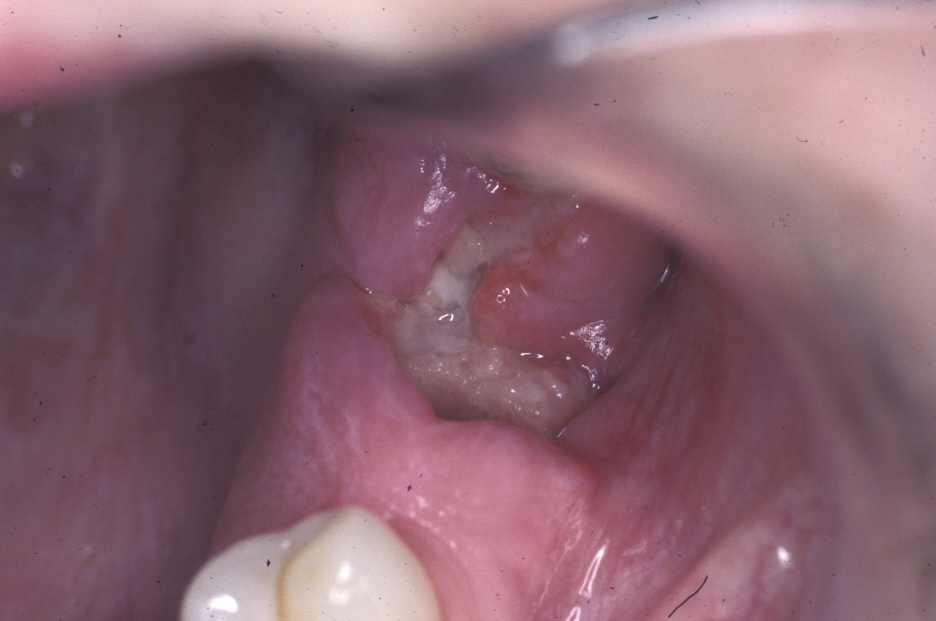

Torus

A torus is a bony exostosis (outgrowth) of the jaw. Torus palatinus occurs in the centre of the hard palate (see Figure 9), torus mandibularis occurs in the lingual (tongue-side) premolar or molar region of the mandible (see Figure 10). These lesions are entirely benign and only require removal when they are symptomatic or for reasons of prosthetic functionality.

Figure 10: The appearance of torus mandibularis.